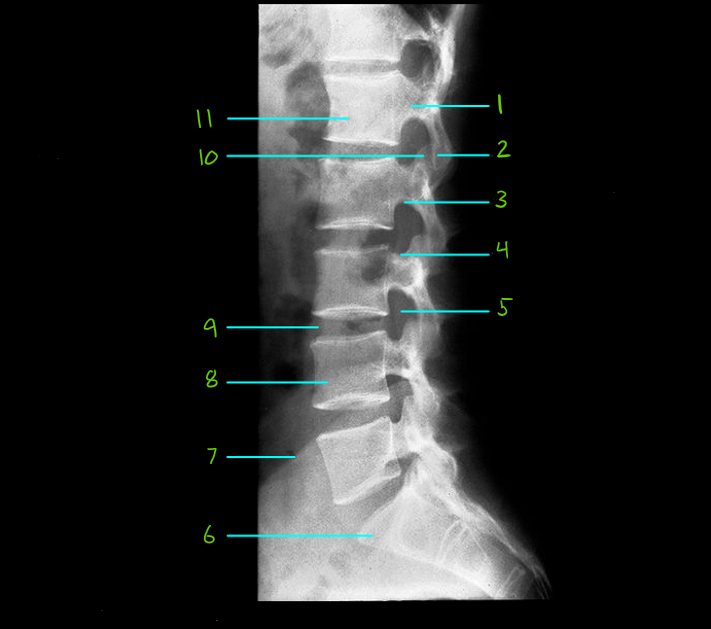

What is #1

Pedicle

What is #2

Inf. articular process

What is #3

Inf. vertebral notch

What is #4

Sup. vertebral notch

What is #5

Intervertbral foramen

What is #6

Sacrum

What is #7

Iliac crest

What is #8

Body of L4

What is #9

L3 intervetrabral disc

What is #10

Sup. articular process

What is #11

Body of L1